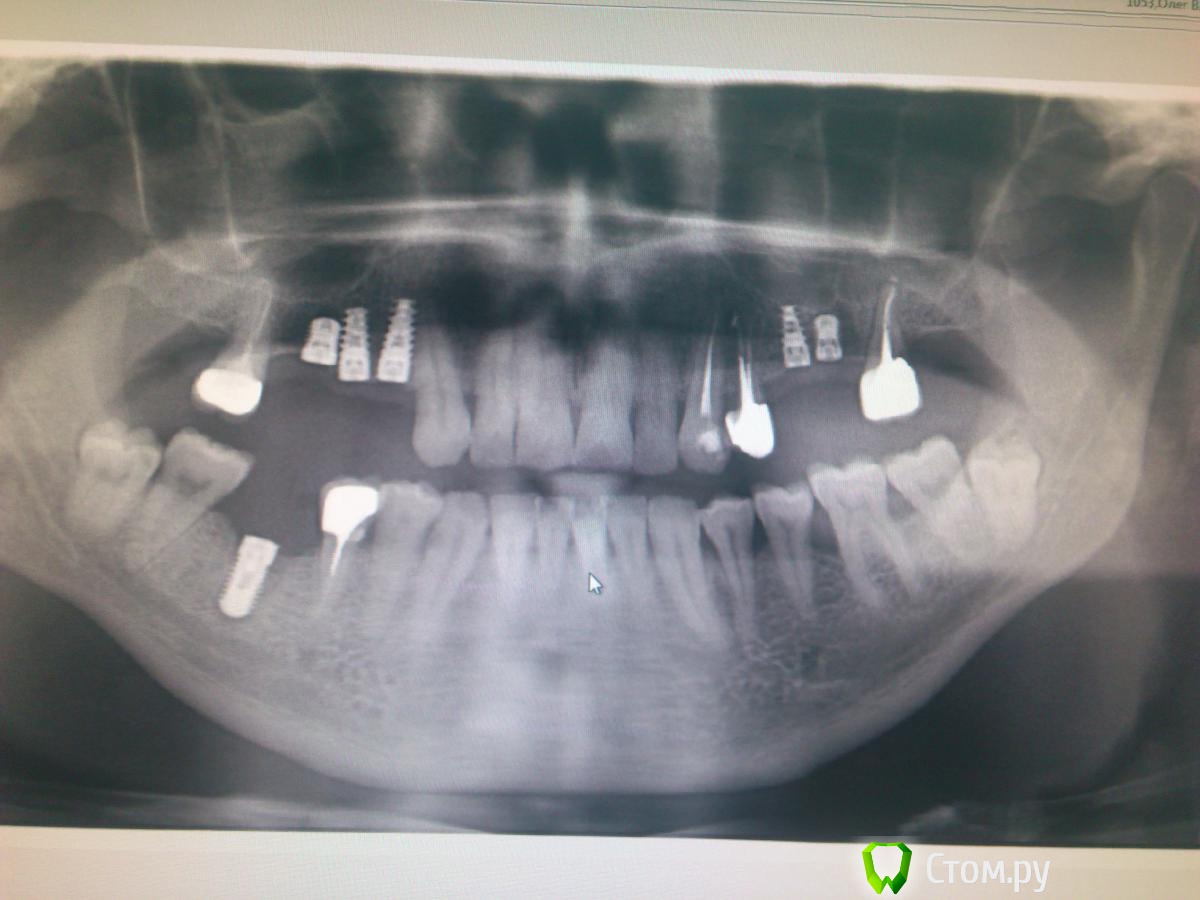

anastasik_ Опубликовано 6 мая, 2014 Поделиться Опубликовано 6 мая, 2014 Добрый вечер коллеги. Я начинающий ортопед. Сегодня в клинике наткнулась на снимок пациента, которого мне предстоит протезировать, и возникли "некоторые" сомнения...Вопрос:1)как оцениваете работу имплантолога, особенно в 1 сегменте?2)какие возникнут проблемы при протезировании в данном случае?Заранее спасибо. Ссылка на комментарий

diesel87 Опубликовано 6 мая, 2014 Поделиться Опубликовано 6 мая, 2014 А что на синус-лифт пациента не удалось мотивировать? В 3-ем сегмента случаем не зубо-альвеолярное выдвижение? Ссылка на комментарий

Mane Опубликовано 6 мая, 2014 Поделиться Опубликовано 6 мая, 2014 План минимум - слева вверху крайний слева и следующий, справа вверху крайний справа и нижний на выход. План максимум - все болты на выход. Увы и ах 3 Ссылка на комментарий

Orient Опубликовано 6 мая, 2014 Поделиться Опубликовано 6 мая, 2014 выдвижение есть,такое бывает)а вот импланты очень близко друг к другу.ждите проблемы потом.если будите протезировать. Ссылка на комментарий

kriokov Опубликовано 6 мая, 2014 Поделиться Опубликовано 6 мая, 2014 в 1 и 2 "кучновато", и кость внушает опасения в позиции винтов 16 и 26 Ссылка на комментарий

Mane Опубликовано 6 мая, 2014 Поделиться Опубликовано 6 мая, 2014 На нижнем резорбция после откидывания лоскута будет до 2-х мм. Рентген немножко скрадывает недуг Ссылка на комментарий